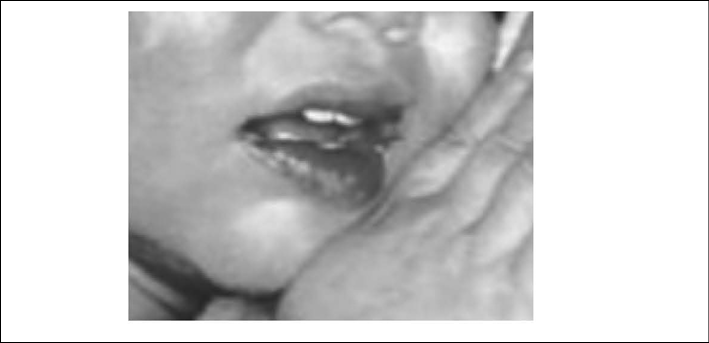

- Oropharyngeal changes consisting of strawberry tongue, erythema of oropharynx, and drying, cracking, and fissuring of the lips (90% of cases) (see Figures 2 and 3);27

Figure 2. Mucous Membrane Changes: Strawberry Tongue

Figure 3. Mucous Membrane Changes: Pharyngeal Erythema, Cracked Lips